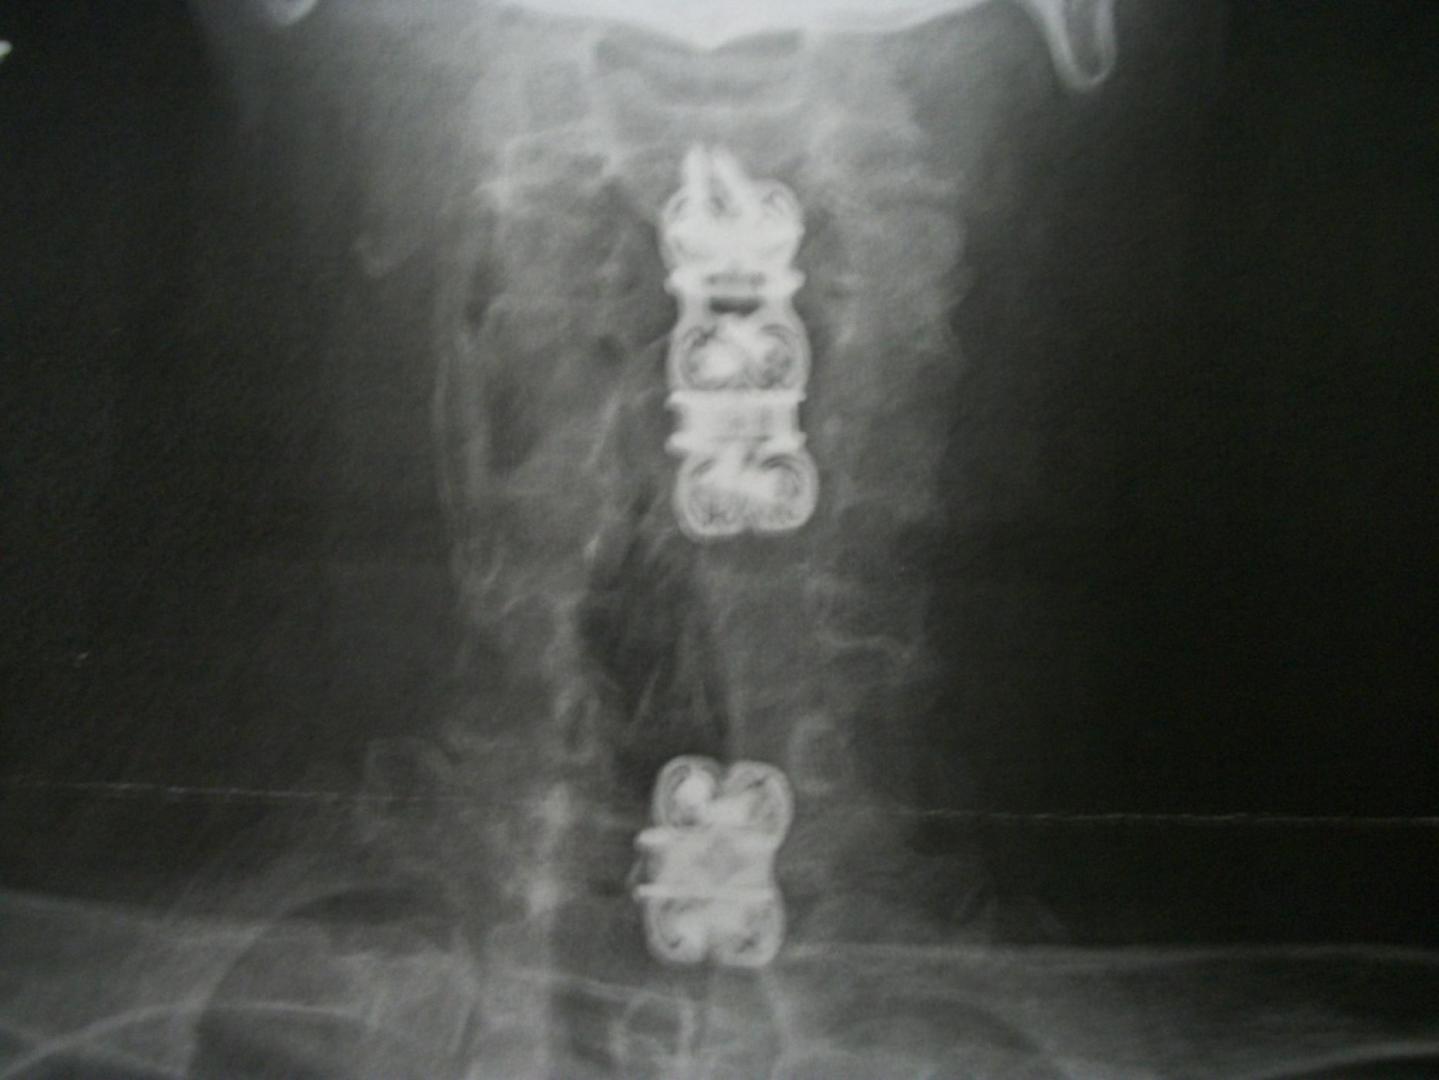

mod3l Lover Posted April 20, 2016 Author Posted April 20, 2016 (edited) Hey Kerry, Truth be told, they are the same old worn out hands, but they are working better again! 10 screws, and 3 titanium plates later. David S. Edited April 20, 2016 by mod3l Lover